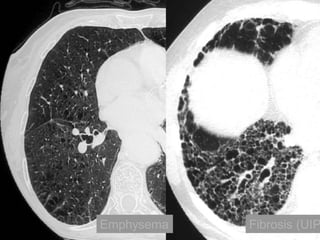

NSIP with superimposedcentrilobular emphysema

• Cigarette smoking •Ageing (presbyteric) lung “expected” changes

Examples of coexistence: •Non-specific interstitial pneumonia (NSIP) - usual interstitial pneumonia (UIP) • Smoking related interstitial diseases – RB-ILD / NSIP / Langerhan’s / emphysema 2 1